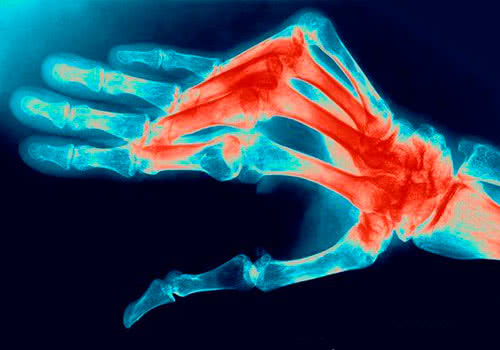

В случае наличия симптомов полиартрита на протяжении одного года и более длительного времени следует проводить рентгенографию рук и ступней. Своевременная диагностика полиартрита имеет очень большое значение. Ведь только при правильной и оперативной терапии больной сможет упредить появление повреждений суставов и иных серьезных нарушений.

Рентгенография позволяет выявить отсутствие деформирующих явлений в суставах. Деформация обычно не наблюдается. Так как рентген свидетельствует об отсутствии значимых деформаций.

Главную роль в постановке диагноза РА играют биохимический анализ крови, рентгенологические суставные изменения и вышеперечисленные симптомы.